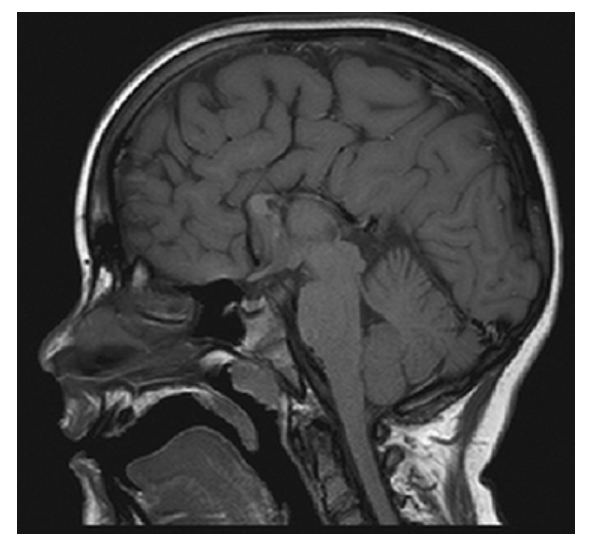

Agenesis of the Corpus Callosum. Sagittal T1W image shows congenital absence of the corpus callosum with radially oriented gyri and the absence of the cingulate gyrus.